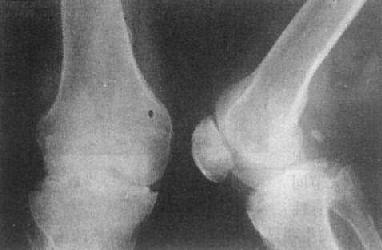

关节破坏——膝关节结核

图2-1-14 关节破坏——膝关节结核

膝关节关节间隙变窄,关节面边缘有虫蚀状骨破坏